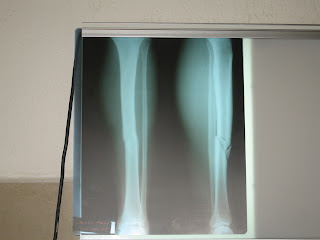

Em um pleno dia resolvemos ir a Cancun para tirar umas fotos e tambem comprar um adesivo da bandeira mexicana para poder colar na moto ,foi quando ao retornarmos a villa onde estavamos ficando, que ficava aproximadamente 30 kms de Cancun,que aconteceu o acidente ,estavamos numa rua onde avia 3 faixas eu estava na mais lenta da esquerda ,um taxi na do meio e um outro carro na esquerda foi quando nao sei o que ouve que o taxi bateu na traseira do outro carro e atravessou na nossa frente sem olhar se tinha alguem passando por ali ,foi quando me choquei com ele na lateral traseira e fraturei minha perna,depois de alguns fui para o hospital onde fui preparado para uma cirugia isso tudo aconteceu por volta de 12:00 hrs e fui para a sala de operacao por volta das 17:00hrs ,ao sair de la estava com um pino de 40 cm na canela e 4 parafusos e parecendo com a perna do wolverine dos Xmens ,pensei em ate mudar meu nome para Pezaoverine hehehehehe.

Voltamos pra Londres onde temos nossa residencia e ficamos por la alguns tempo onde a Elenice voltou a trabalhar por 3 meses e eu fiquei fazendo meus exames e outra cirugia pra a retirada de 2 parafusos ,dai ja que estava tudo certo ja estava conseguindo a andar e teria que voltar ao Mexico para retirar a moto porque o visto da moto a permissao temporaria dela no Mexico venceria no dia 15 de maio entao marcamos nossa passagem de volta para o dia 18 de abril ,foi quando o vulcao na Islandia entrou en erupicao e por lancar muita cinzas no ar todos os aeroportos da europa forao cancelados e com isso nosso voo tambem, depois remarcamos nossa volta para duas semanas depois para o dia 4 de maio entao so teriamos alguns dias para arrumar a moto e sair do mexico ,foi quando no dia 4 de maio quando ja iamos para o aeroporto vimos na tv que os aeroportos comecarao a ser cancelados novamente ja tinha sido fechados 2 aeroportos no norte do reino unido ,dai comecou toda aflicao porque nosso voo era para as 9:00hrs,mais enfim tudo deu certo retornamos a cancun arrumei minha moto so faltava uma bateria pra ela foi quando paguei para o mecanico pra pedir uma nova pra mim e ele disse que ja tinha pedido e so q ele vendeu a bateria para outra pessoa e a minha iria demorar 5 dias para chegar foi quando resolvi esperar que foi um grande erro porque essa bateria nunca chegou ele nunca respondeu minhas ligacoes e desapareceu com meu didin heheehhehe mais tudo bem talves ele precisava desse didin mais do que eu .